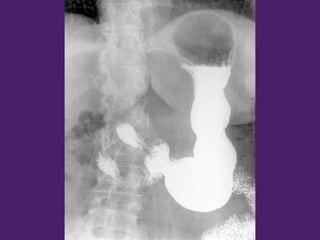

¡¡¡Bonus track 2!!!!!

Tránsito esófagogastroduodenal